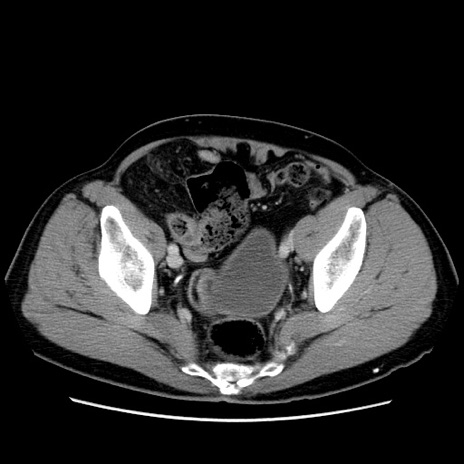

症例34(横断像)

【症例】60歳代 男性

【主訴】右鼠径部膨隆

【現病歴】1年程前より右鼠径部膨隆あり。自己にて還納可能だったため放置していた。3時間前より右鼠径部の脱出を認め、還納困難となり受診。

【既往歴】高血圧

【身体所見】右鼠径部に小児頭大の膨隆あり。弾性硬であり、用手還納は困難。左鼠径部にも膨隆を認める。脱出はなし。

【データ】WBC 15500、CRP 測定なし